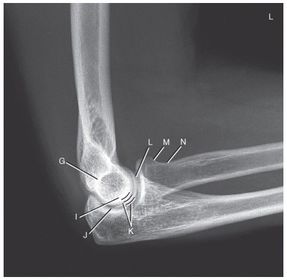

G. superimposed epicondyles of humerus I. trochlear sulcus J. trochlear notch K. outer ridges of capitulum and trochlea L. coronoid process of ulna M. radial head N. radial neck

a. outer ridges of capitulum and trochlea b. trochlear notch c. trochlear sulcus

1. trochlear sulcus 2. outer ridges of capitulum and trochlea 3. trochlear notch